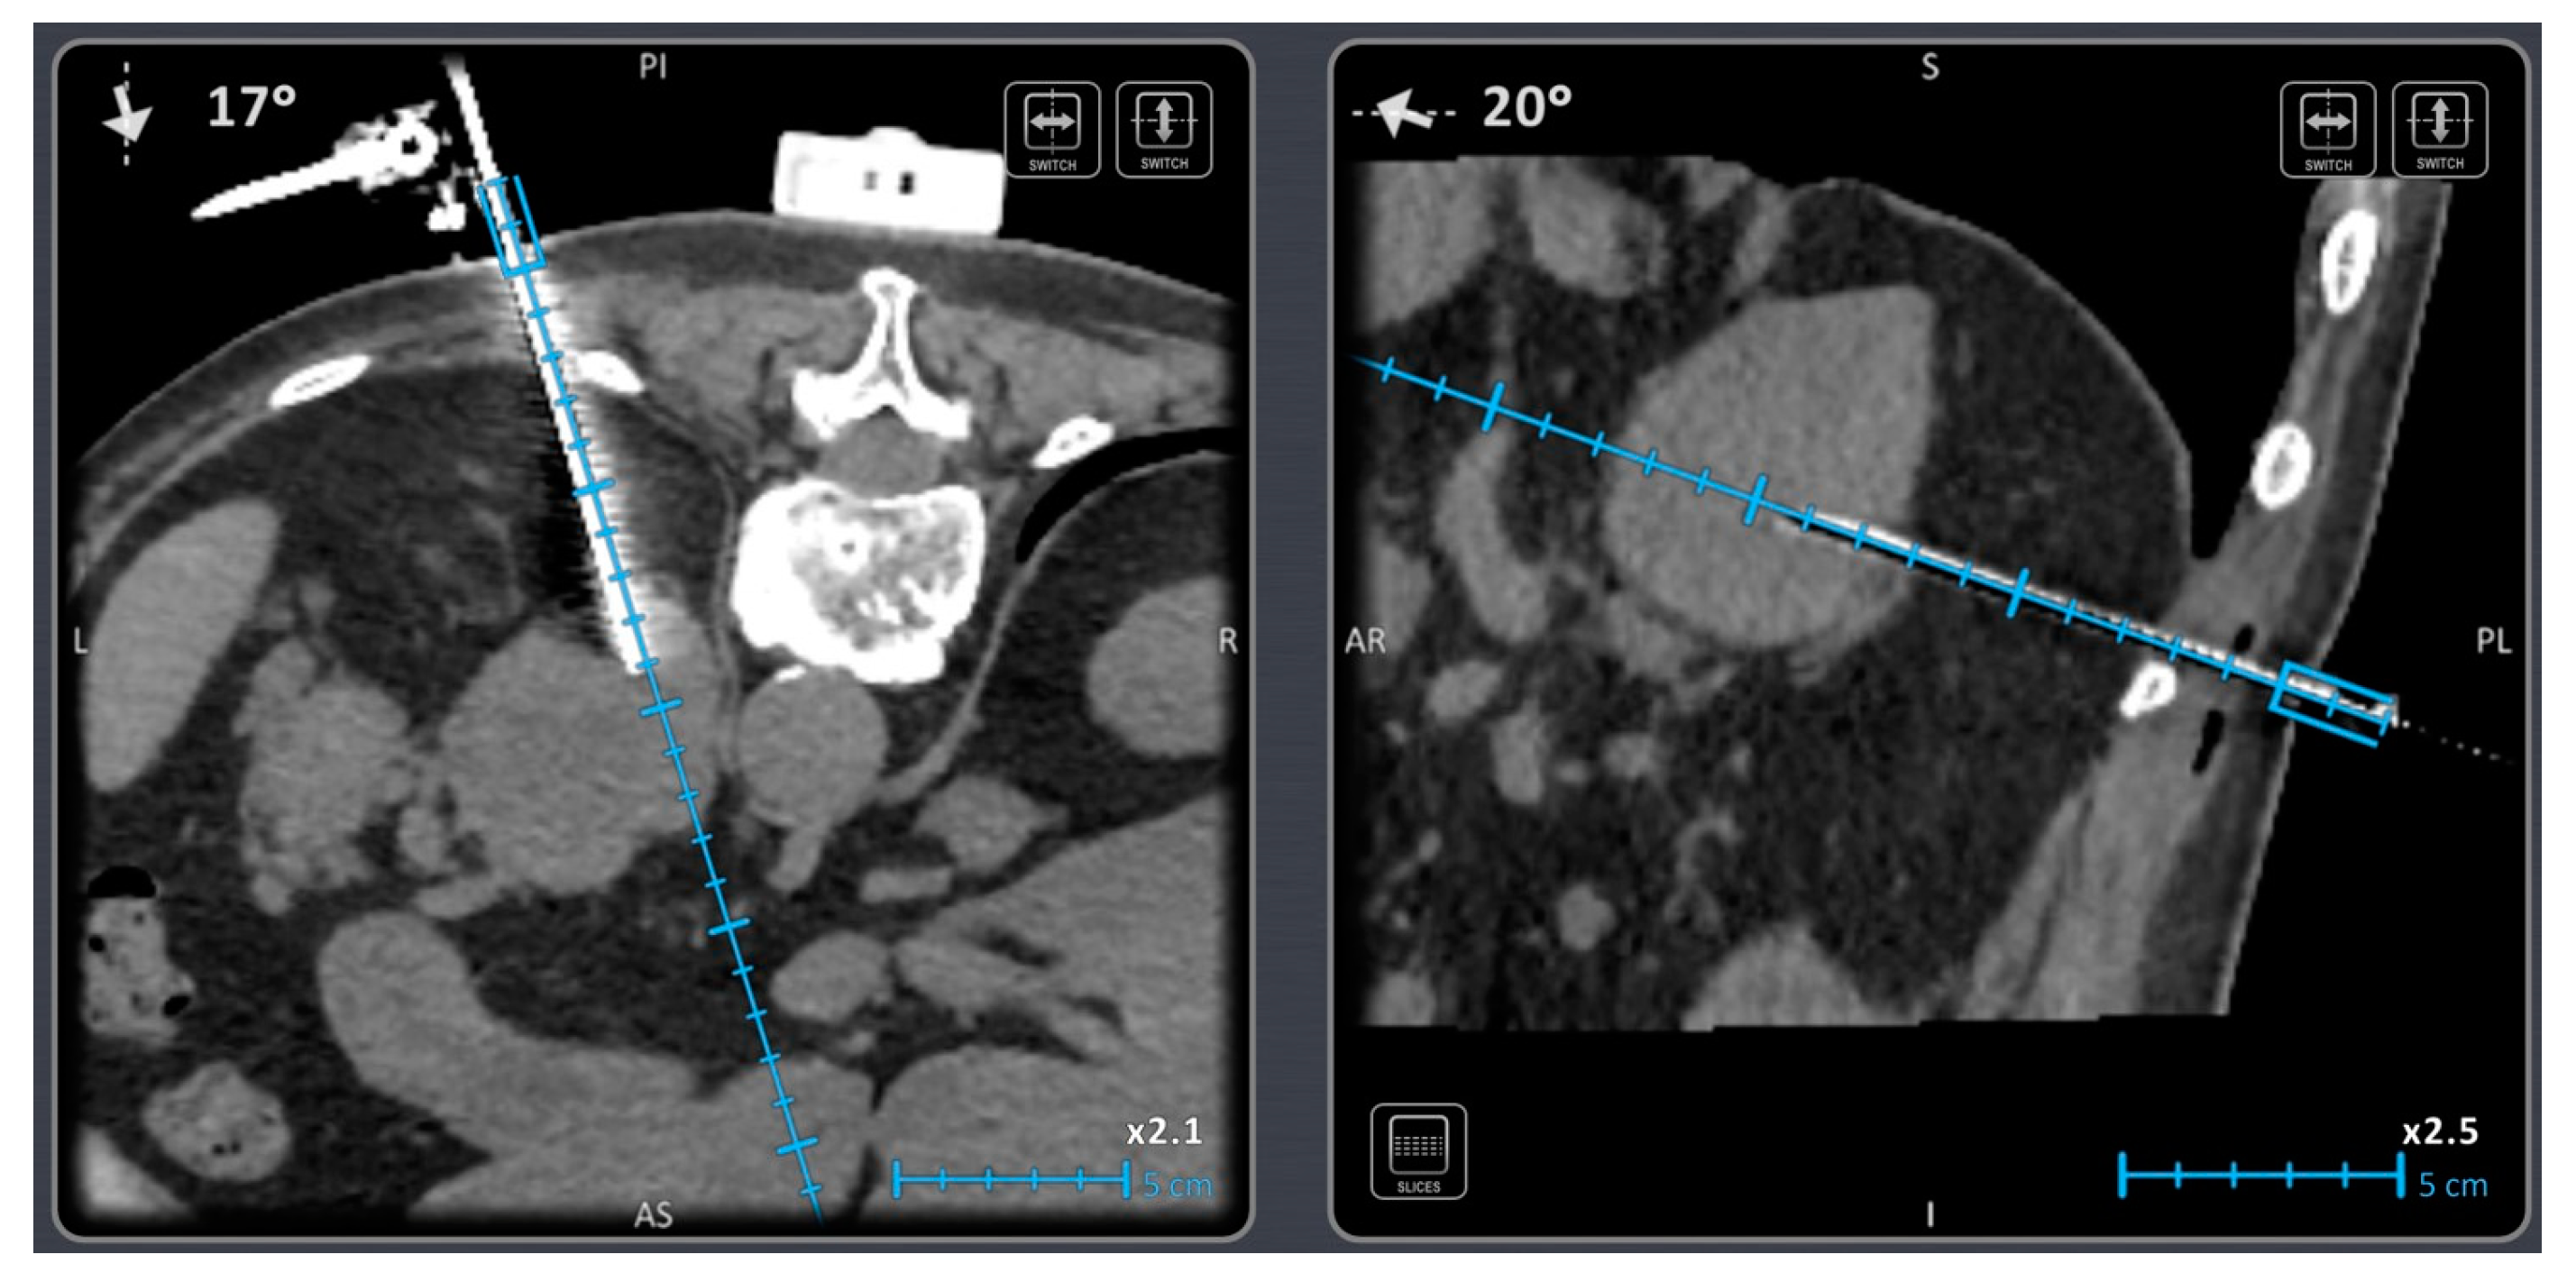

- Bale, R.; Widmann, G.; Stoffner, D.R. Stereotaxy: Breaking the limits of current radiofrequency ablation techniques. Eur. J. Radiol. 2010, 75, 32–36. [Google Scholar] [CrossRef] [PubMed]

- Bale, R.; Laimer, G.; Schullian, P.; Alzaga, A. Stereotactic ablation: A game changer? J. Med. Imaging. Radiat. Oncol. 2023. [Google Scholar] [CrossRef] [PubMed]